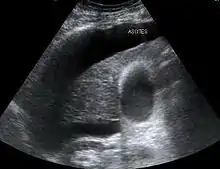

The use of ultrasound has become the standard of care when preparing a patient for paracentesis. Confirmation of an ascitic effusion reduces the risks associated with a dry or blind tap of the abdomen. Anatomic landmarks, such as the midline linea alba approach, were traditionally used as reference points for needle insertion. Phased array or curvilinear ultrasound transducers are typically used in the hospital and outpatient setting to identify ascites in the abdominal cavity. Fluid within the abdominal cavity appears hypoechoic or anechoic (black) on ultrasound. Morison's pouch (hepatorenal recess) is a common starting location in concordance with ultrasound FAST (focused assessment with sonography for trauma) exam. Fluid collection can occur in a number of different locations and may be difficult to find, especially if the patient only exhibits a small volume of ascites. Measurement of the amount of fluid within the abdominal cavity is not necessary or very successful. Identification of sufficient fluid within the abdominal cavity for fluid analysis or to achieve a therapeutic benefit is all that is required to proceed to paracentesis. Ultrasound guidance of the paracentesis can also be used as an additional safety measure to ensure the needle stays within the ascitic fluid and avoidance of important vessels within the abdominal cavity. [5]